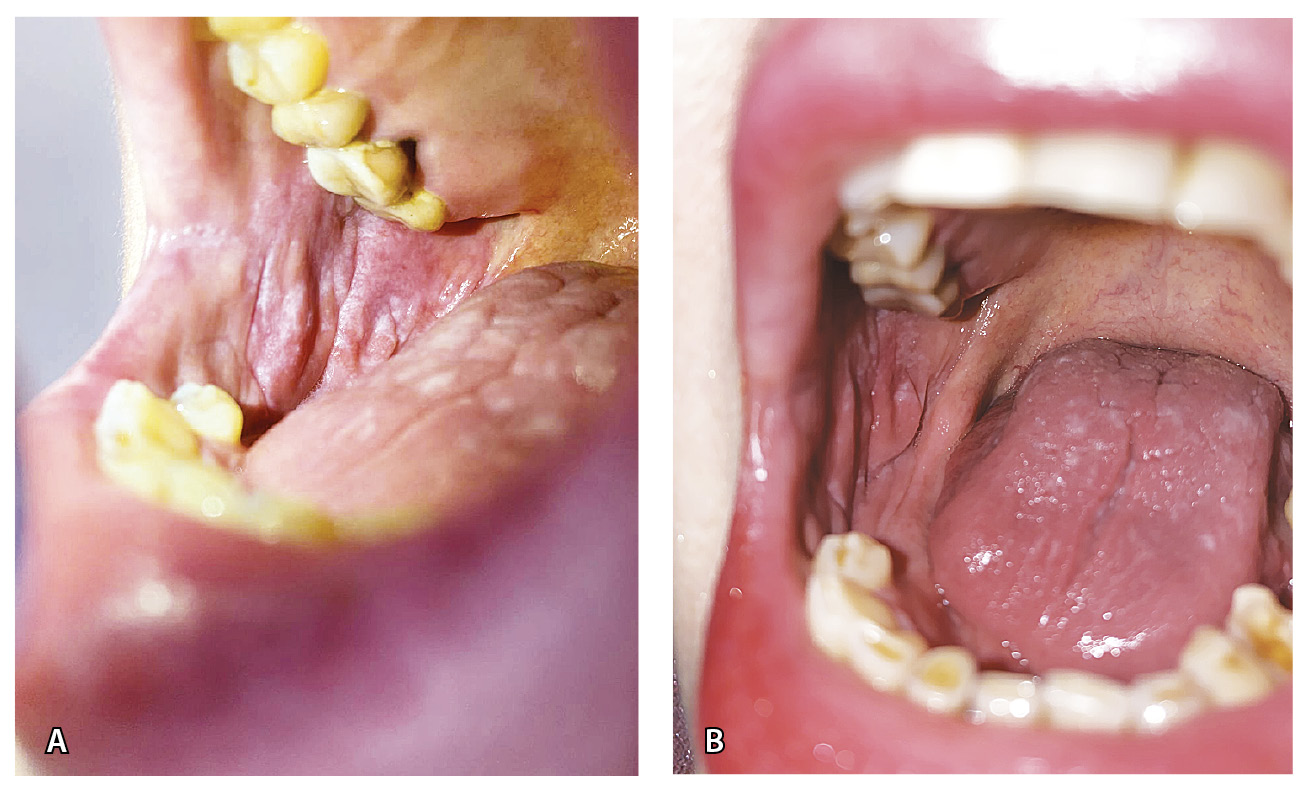

Кожа лица слегка отечна и гиперемирована, лицо имело «лунообразную» форму. На коже туловища в области груди и боковых поверхностей живота отмечались папулы розового цвета, единичные бляшки размером 1,0 × 1,0 см розового цвета с наслоением белых чешуек на поверхности (рис. 1). Феномен псориатической триады отрицательный. На коже волосистой части головы в затылочной области – очаг размером 3,0 × 2,0 см, в центре которого наслоение плотных серебристых чешуек, по периферии – область гиперемии (рис. 2А). На ладонной и боковой поверхности первого и второго пальцев правой кисти – участки гиперкератоза желтого цвета с белыми чешуйками (рис. 3). На коже паховой области, больших половых губ – папулы синюшного цвета, полигональные вытянутые с блеском при боковом освещении. На слизистой больших и малых половых губ, ануса – белесоватые папулы, сливающиеся в бляшки (рис. 4А). На слизистой щек – белесоватые папулы, сливающиеся в ретикулярные бляшки, отдельные белесоватые папулы – на спинке языка (рис. 5). На красной кайме нижней губы в латеральных частях – белесоватые вытянутые бляшки размером 1,0 × 0,5 см. Субъективно пациентка отмечала зуд в области гениталий.

Рис. 5. Лихеноидные высыпания на слизистой оболочке полости рта и языка (правая щека): А – до лечения, Б – после лечения

Через 6 недель после начала наружной терапии отмечена положительная динамика: разрешение высыпаний на слизистой гениталий, пигментные пятна на месте папул на коже паховой области и больших половых губ (рис. 4Б), уменьшение количества высыпаний на слизистой полости рта и языка (рис. 6), разрешение бляшек на красной кайме нижней губы, разрешение центральной части очага в затылочной области (рис. 2Б). Единичные папулы и бляшки на коже туловища и очаги на пальцах кисти сохранялись.

Рис. 6. Лихеноидные высыпания на слизистой оболочке полости рта и языка (левая щека): А – до лечения, Б – после лечения

Для лечения псориазиформных очагов мы рекомендовали использовать метилпреднизолона ацепонат, что через 6 недель привело к регрессу части высыпаний, в частности, центральной зоны очага на волосистой части головы в затылочной области, однако некоторые бляшки на коже туловища и участки гиперкератоза на пальцах кисти сохранялись. Значительный эффект был получен в результате применения на лихеноидные высыпания на коже и слизистых оболочках 0,1% мази такролимуса. Регресс высыпаний на слизистой гениталий, папул в паховой области, бляшек на красной кайме нижней губы констатировали через 6 недель ежедневного использования, на слизистой полости рта и языка количество высыпаний существенно уменьшилось. Прием иматиниба в дозе 400 мг/сут пациентка не прекращала. Мазь такролимуса является терапией первой линии при поражении слизистых оболочек красным плоским лишаем и успешно применяется при данном заболевании. Мы впервые эффективно использовали ее для лечения лихеноидных лекарственно-индуцированных высыпаний на слизистых оболочках на фоне приема иматиниба, хотя в доступной нам литературе подобного опыта не встретили.